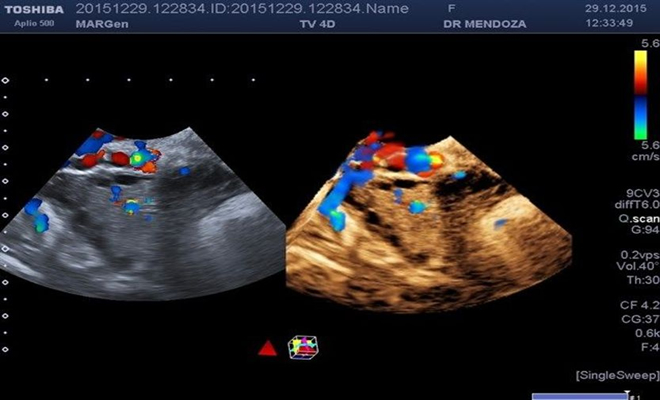

La presente investigación descubrió el impacto de la hormona anti-Mülleriana (AMH) y la midió en una cohorte de mujeres embarazadas con el síndrome versus un grupo control de mujeres embarazadas sanas. Se encontró que las concentraciones de AMH durante el embarazo son significativamente más altas en mujeres con el síndrome en comparación con las mujeres sin defectos reproductivos (30% más).